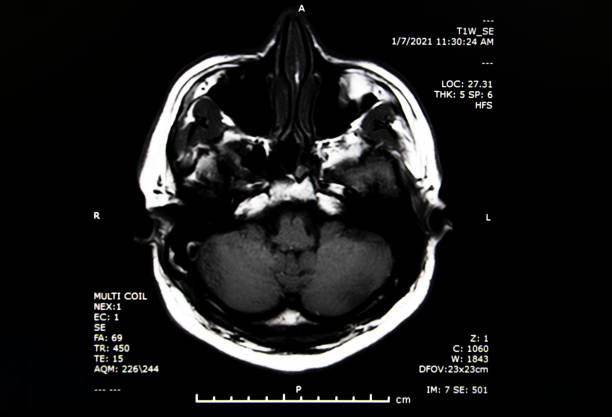

뇌경색 후유증은 심각한 장애를 남길 수 있는 신체적, 정신적 문제를 야기할 수 있는 중요한 주제입니다.

뇌경색 의심이 된다면 빠르게 대응해서 치료를 하는게 좋습니다.

✅뇌경색 후유증 종류

뇌경색 후유증은 다양한 증상을 유발할 수 있습니다. 이러한 증상은 흔히 다음과 같이 나눌 수 있습니다.

1. 전두엽 손상

뇌경색 후, 이마 부위에 손상이 생기면 하체의 힘이 약해질 수 있습니다. 이로 인해 환자는 걷거나 움직일 때 한 쪽으로 기울거나 반쪽의 마비가 발생할 수 있습니다. 대소변의 장애, 성격 변화, 사고력 저하, 집중력 감소 등과 같은 부작용도 나타날 수 있습니다.